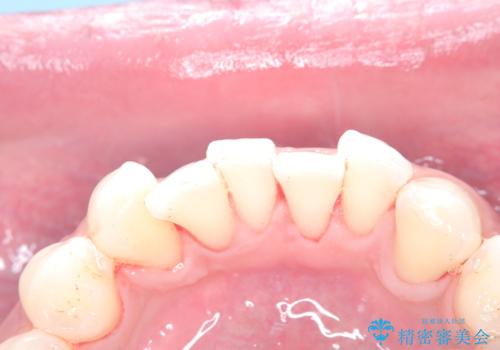

歯の着色にはエアーフロー

- 治療計画

- 濃い着色はホワイトニングでは落ちないためエアーフローをお勧めいたします。定期的にホワイトニングをやっているので白さはキープしていた方なので仕上がりは綺麗になりとてもご満足いただけました。

とてもご満足いただけました。